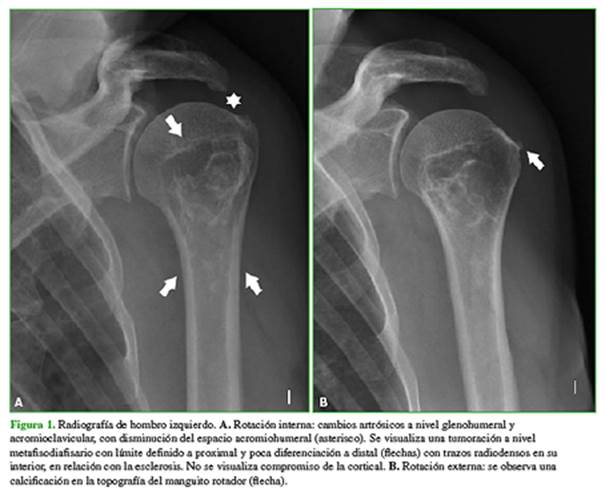

En el examen físico, no se palpan tumoraciones. Tanto la movilidad pasiva y como la activa están disminuidas y las pruebas para manguito rotador son positivas. Se solicitan una radiografía de hombro izquierdo en rotación interna y externa (Figura 1) y una ecografía de hombro (Figura 2).

HallazgoS e interpretación de los estudios por imágenes